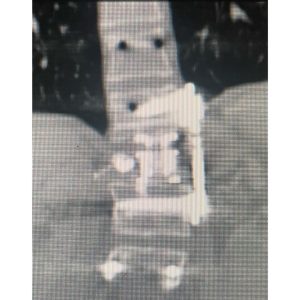

She was taken to surgery about 4 1/2 years ago and the entire L1 vertebrae and tumor was surgically removed from the front and back with the help of a vascular surgeon. I had to place extensive hardware from the front and back to support the missing vertebrae. She recovered well. Recent CT scans showed no further cancer in the spine. (Photos 3-5.)